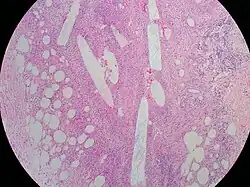

A breast biopsy is a medical procedure used to remove a small sample of breast tissue to examine it more closely under a microscope. It is usually done after a suspicious lesion is discovered on either mammography or ultrasound to get tissue for pathological diagnosis.[1] Several methods for a breast biopsy now exist.[2] The most appropriate method of biopsy for a patient depends upon a variety of factors, including the size, location, appearance and characteristics of the abnormality.[3] The different types of breast biopsies include fine-needle aspiration (FNA), vacuum-assisted biopsy, core needle biopsy, and surgical excision biopsy.[3][4][5] Breast biopsies can be done utilizing ultrasound, MRI or a stereotactic biopsy imaging guidance.[2][5][4][6] Vacuum assisted biopsies are typically done using stereotactic techniques when the suspicious lesion can only be seen on mammography.[5] On average, 5–10 biopsies of a suspicious breast lesion will lead to the diagnosis of one case of breast cancer.[7] Needle biopsies have largely replaced open surgical biopsies in the initial assessment of imaging as well as palpable abnormalities in the breast.[8]